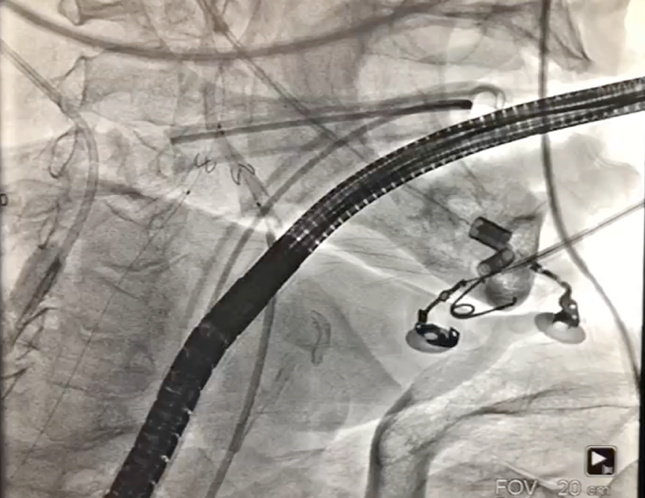

经右股动脉将Emboshield Nav6放栓塞装置输送至左、右颈内动脉。

图片